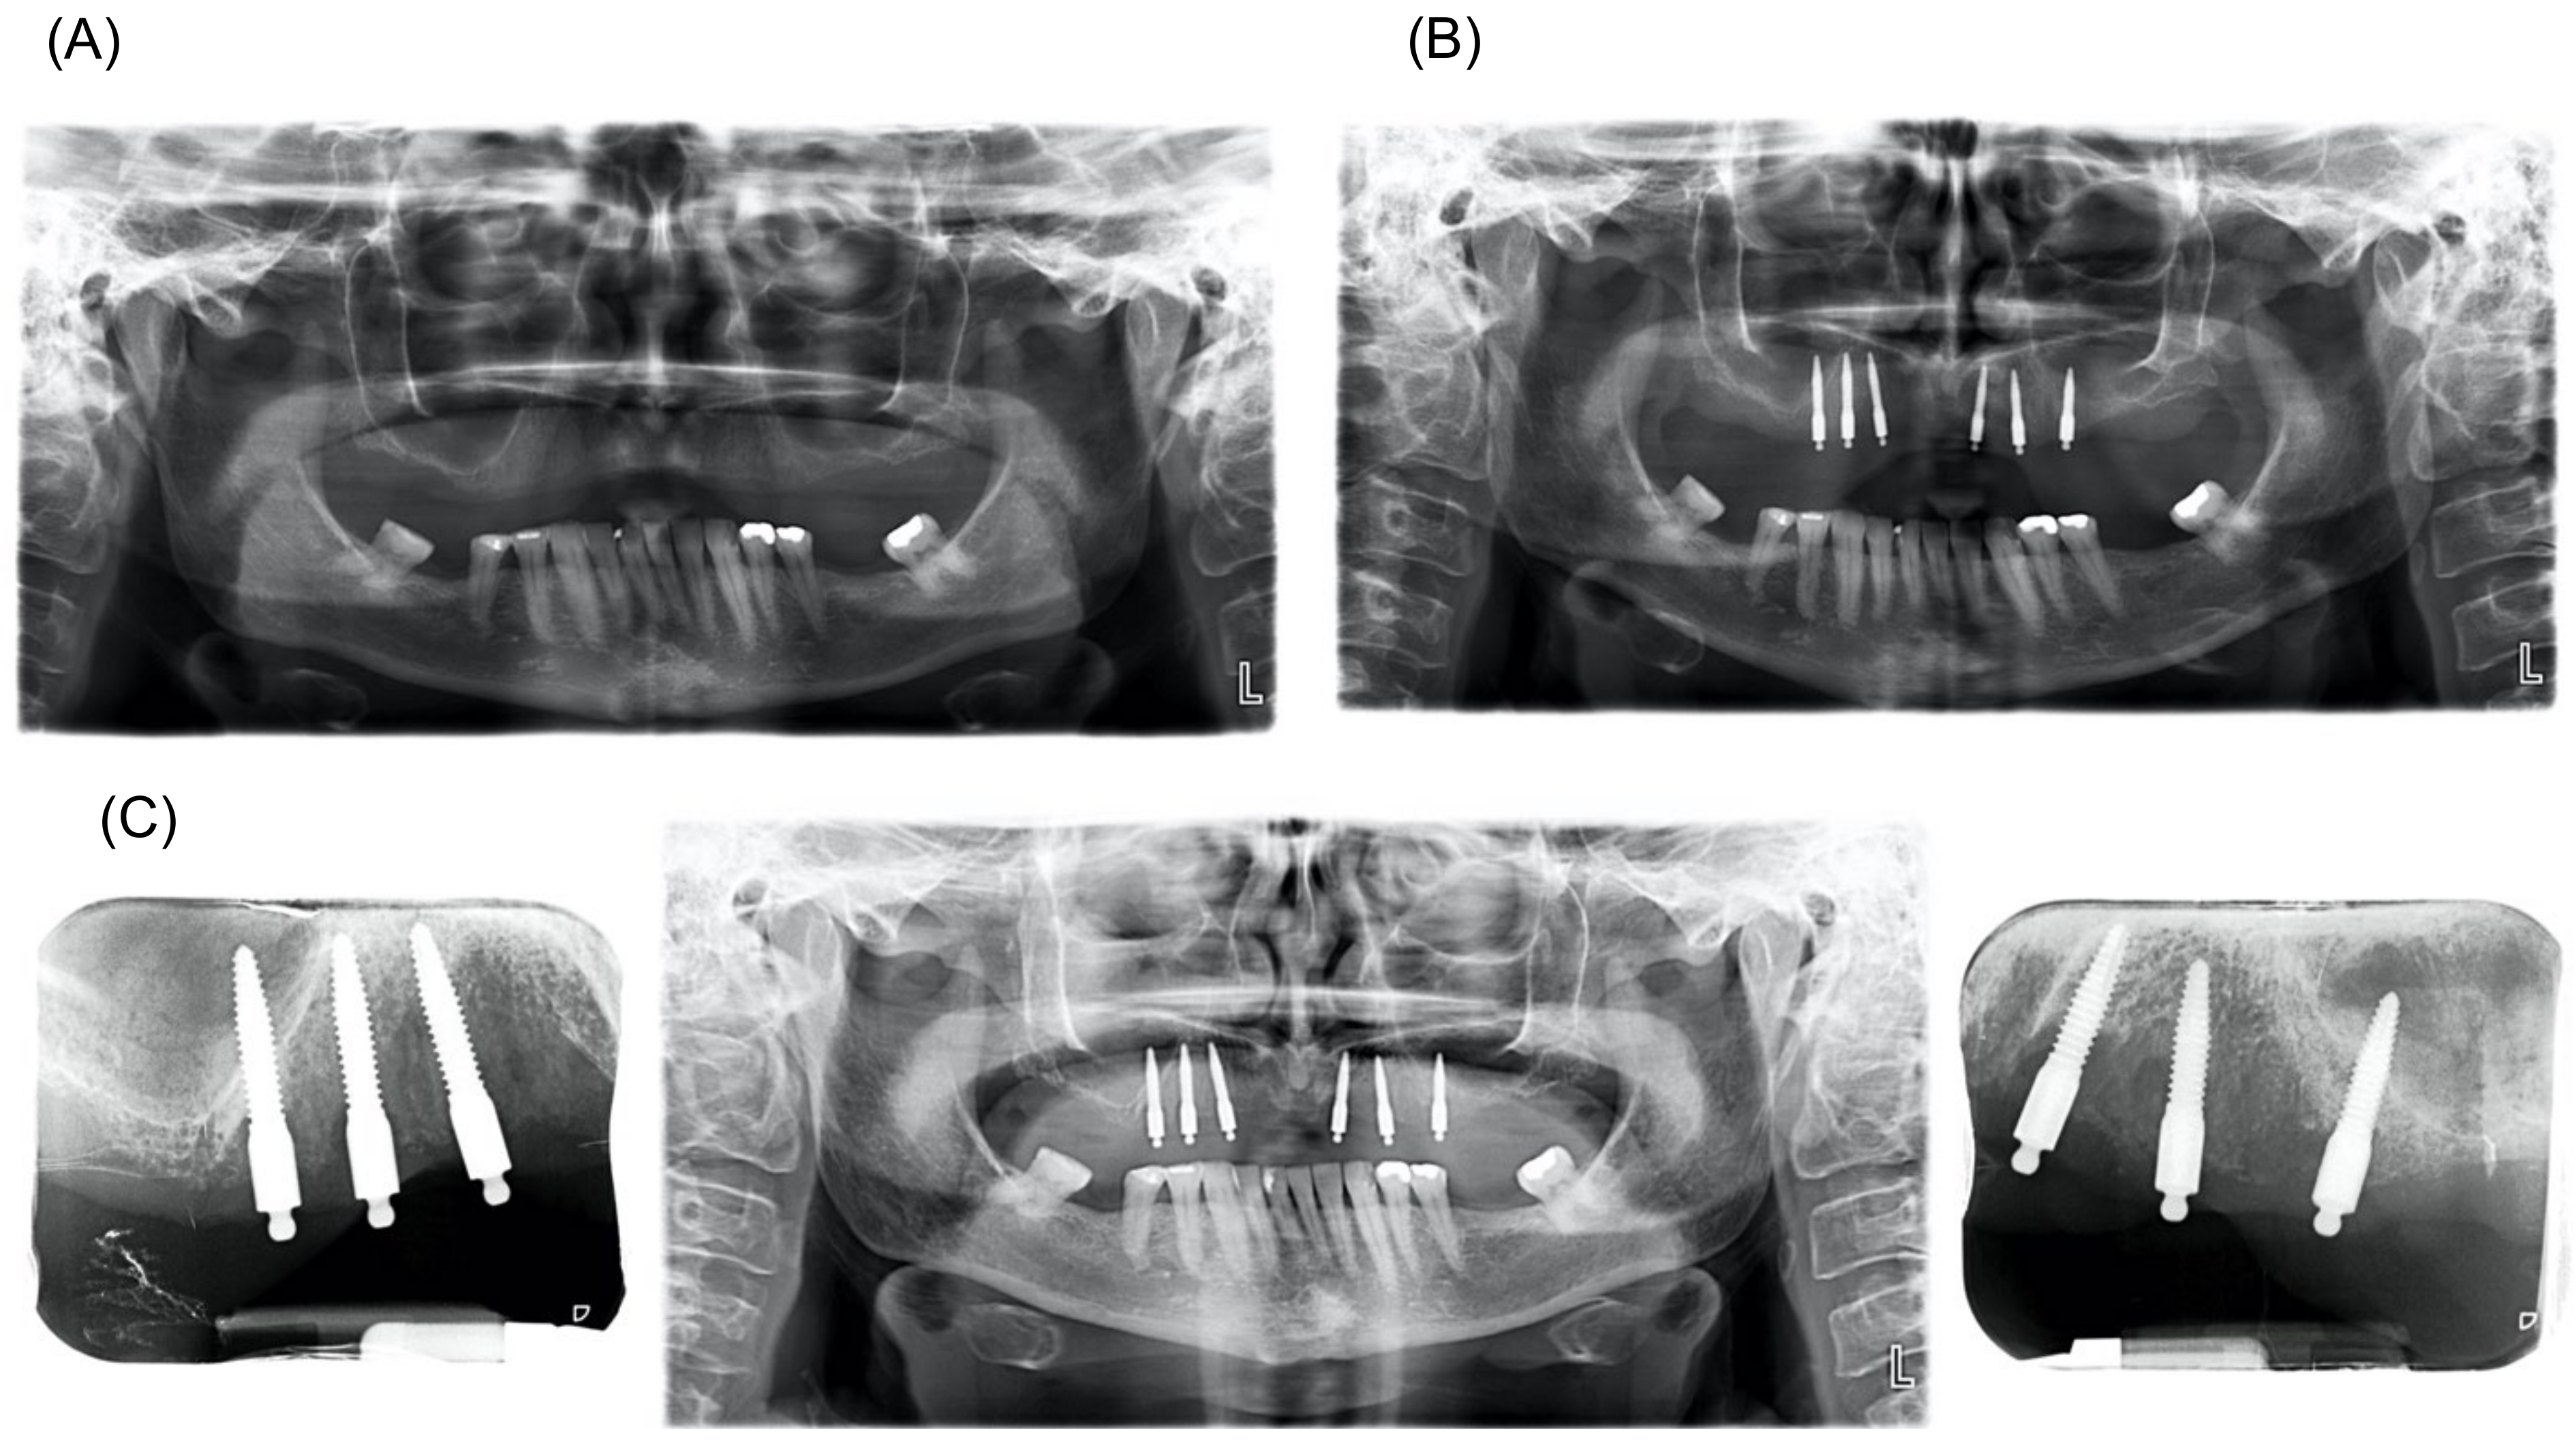

Case Report